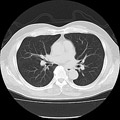

胸腹部CT検査:17,600円(胸部・腹部それぞれ単独での撮影も可能です)

胸部CTは肺疾患(肺がん・肺気腫など)の検索にお勧めします。喫煙されている方は特にお勧めします。腹部CTは肝・胆・膵・腎・脾臓の異常の早期発見に有効です。

レポートによる結果報告となります。